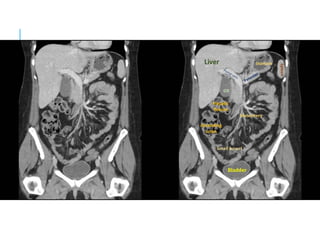

CT SCAN

CT ANGIOGRAM